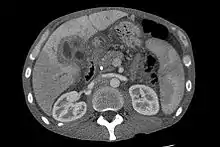

Ultrasound of the liver and biliary tree is often used as the initial imaging modality in people with suspected obstructive jaundice.[49][50] Ultrasound can identify obstruction and ductal dilatation and, in some cases, may be sufficient to diagnose cholangiocarcinoma.[51] Computed tomography (CT) scanning may also play an important role in the diagnosis of cholangiocarcinoma.[52][53][54]

Imaging of the biliary tree

While abdominal imaging can be useful in the diagnosis of cholangiocarcinoma, direct imaging of the bile ducts is often necessary. Endoscopic retrograde cholangiopancreatography (ERCP), an endoscopic procedure performed by a gastroenterologist or specially trained surgeon, has been widely used for this purpose. Although ERCP is an invasive procedure with attendant risks, its advantages include the ability to obtain biopsies and to place stents or perform other interventions to relieve biliary obstruction.[12] Endoscopic ultrasound can also be performed at the time of ERCP and may increase the accuracy of the biopsy and yield information on lymph node invasion and operability.[55] As an alternative to ERCP, percutaneous transhepatic cholangiography (PTC) may be utilized. Magnetic resonance cholangiopancreatography (MRCP) is a non-invasive alternative to ERCP.[56][57][58] Some authors have suggested that MRCP should supplant ERCP in the diagnosis of biliary cancers, as it may more accurately define the tumor and avoids the risks of ERCP.[59][60][61]